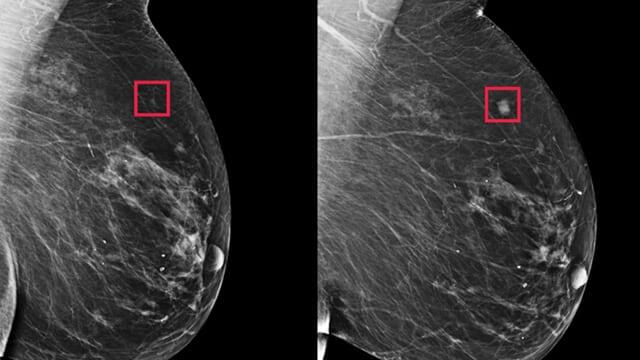

Самые ранние признаки рака молочной железы

В этой статье рассматриваются ранние признаки рака молочной железы, кто может подвергаться риску и что следует делать людям, если они заметили один или несколько из этих предупреждающих признаков. Определенные изменения в груди могут быть ранними признаками рака молочной железы. Знание того, как выглядят и ощущаются эти изменения, может помочь людям как можно скорее получить доступ к правильному лечению.

Понимание различных частей молочной железы и их функций может помочь людям лучше осознавать любые изменения или отклонения. Когда большинство людей думают об обнаружении рака молочной железы, они думают о "шишке" в груди. Это возможный предупреждающий знак, но он не единственный. При этом те же изменения часто являются результатом доброкачественных заболеваний молочной железы. Они не обязательно означают наличие рака. Однако, если человек замечает эти изменения, ему следует обратиться к врачу, чтобы убедиться в этом.